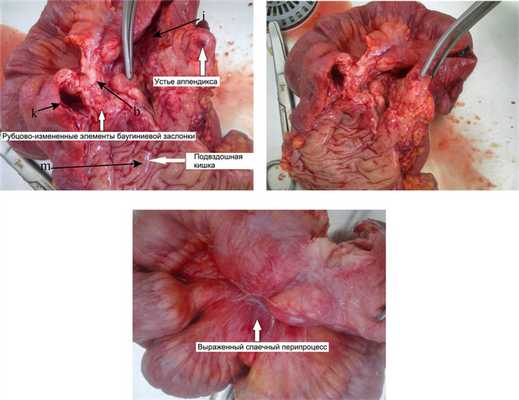

Макропрепарат илеоцекальной области представлял собой конгломерат (рис. 3), Рис. 3. Больная Ч., 34 года. Макропрепараты илеоцекального перехода после правосторонней гемиколэктомии. Фото. b — язва; k — просвет восходящей ободочной кишки; i — просвет слепой кишки; m — просвет подвздошной кишки. состоящий из спаянных между собой петель восходящей ободочной, слепой и подвздошной кишок. При рассечении этого участка определялась значительная плотность ткани, деформация стенки, элементы баугиниевой заслонки не дифференцировались, в районе предполагаемой нижней губы баугиниевой заслонки — глубокая язва, неправильной формы, с плотными краями.

Заключение послеоперационного гистологического исследования удаленного макропрепарата илеоцекального перехода (рис. 4): Рис. 4. Больная Ч., 34 года. Микропрепараты илеоцекального перехода. а — лимфоидно-клеточная инфильтрация; b — лимфоидная гиперплазия; с — склерозирование стенки; d — клетки Пирогова—Лангханса; е — крипт-абсцесс; f — язва; k — бокаловидные клетки. Окраска гематоксилином и эозином; ув. 40 (а, б), ув. 100 (в, г). склерозирование всех слоев стенки с выраженной лимфоцитарной инфильтрацией и очаговой лимфоидной гиперплазией. Определяются гигантские клетки Пирогова—Лангханса, крипт-абсцессы, глубокая язва. Количество бокаловидных клеток сохранено. Данная картина соответствует болезни Крона.